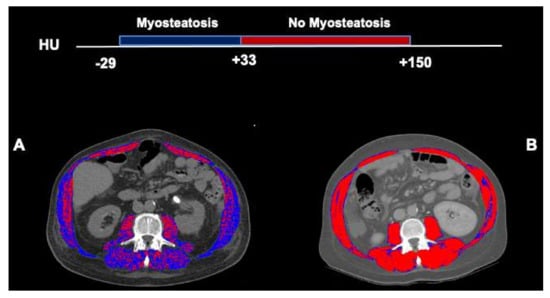

2.2. Computed Tomography Image Analysis